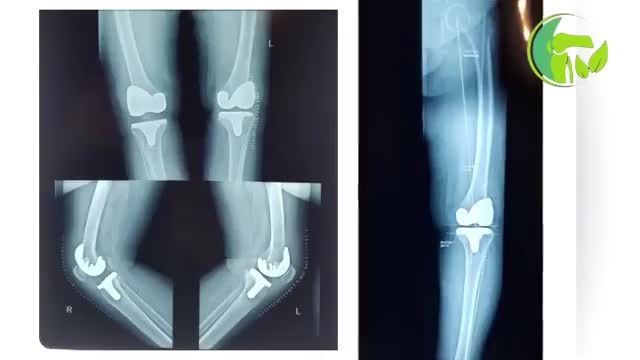

فیلم بدون سانسور قبل و بعد تعویض دوطرفه مفصل زانو